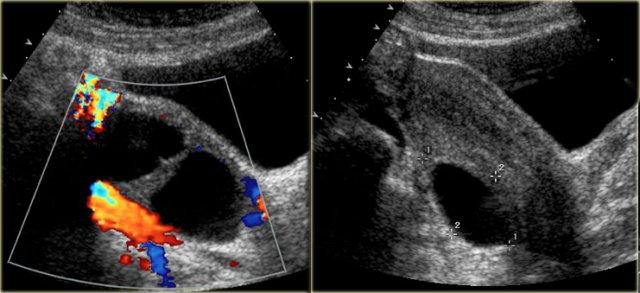

Nang hoàng thể

Hoàng thể có thể bị bít lại và chứa đầy dịch hoặc máu, tạo thành nang hoàng thể.

Các hình ảnh siêu âm qua ngã âm đạo cho thấy một nang buồng trứng phức tạp nhỏ với mạch máu thành nang trên phân tích Doppler năng lượng.

Hình ảnh Doppler vòng tròn đặc trưng này được gọi là dấu hiệu ‘vòng lửa’ (ring of fire).

Lưu ý, có hiện tượng xuyên âm tốt và không có mạch máu bên trong, phù hợp với nang hoàng thể đang thoái triển một phần.

Cần nhớ rằng phụ nữ đang dùng thuốc tránh thai thường sẽ không hình thành hoàng thể, vì thuốc tránh thai ngăn chặn quá trình rụng trứng.

Mặt khác, việc sử dụng thuốc kích thích rụng trứng làm tăng nguy cơ hình thành nang hoàng thể.

Một trường hợp khác với hình ảnh điển hình của dấu hiệu ‘vòng lửa’ trên siêu âm.